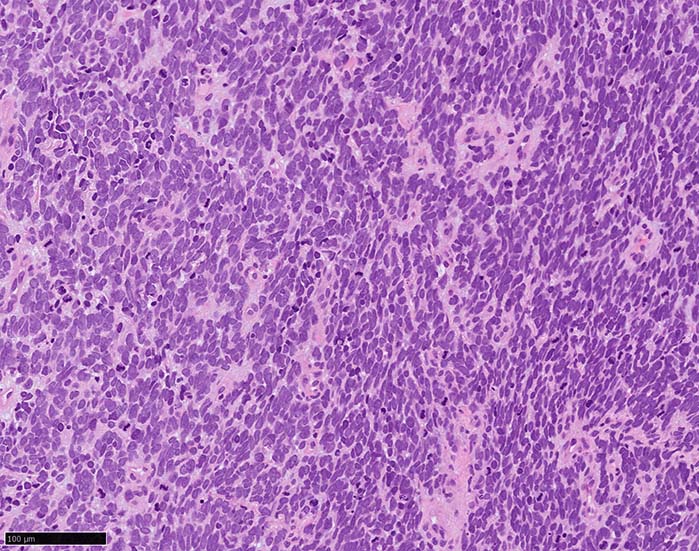

HE

血管を間質にしてround cellsが索状に増殖する所見. rossett様配列がある. CK20は特徴的な dot-like patternを示す. クリックで大きな画像が見られます.

HEx40

HEx200

HEx400